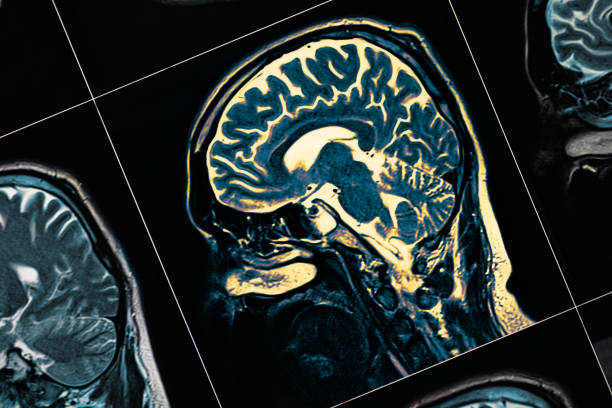

其他專家將參與為您的孩子進行全面的體檢、 血液檢查、心理健康測試、大腦成像測試和其他檢查。它們都是找到正確診斷并制定治療計劃以幫助您的孩子控制疾病的關鍵。